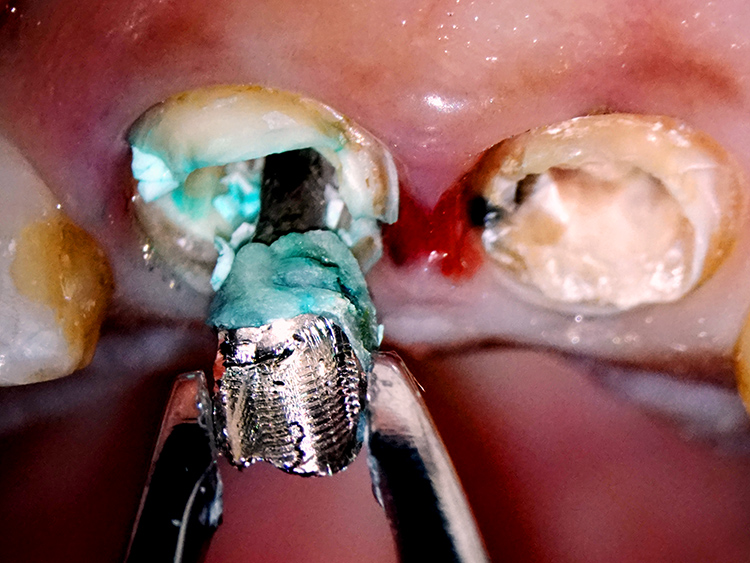

古い金属の土台を除去すると、根の内部に明らかな破折線が認められました。

正面の前歯2本が、ともに重度の歯根破折と診断しました。

歯肉の奥深くまで破折が及んでいるため、この歯を機能的、審美的に回復させることは通常では不可能とも思われるほどの難症例でした。

写真に示されているのは、当院独自の【隔壁テック】と呼ぶ手法です。これは、治療中の前歯が外見上、治療を行っていることが分かりにくいよう工夫されたものです。